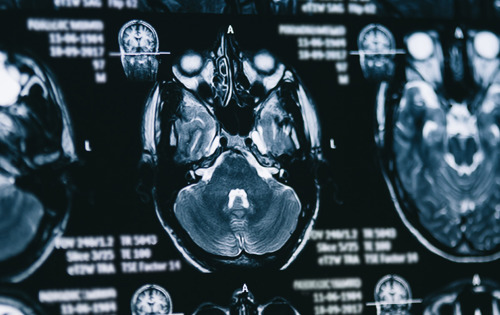

Neben der genetischen Testung empfiehlt der CHMP vor Beginn und während der Behandlung regelmäßige Magnetresonanztomographien (MRTs) zur Überwachung auf ARIA durchzuführen.